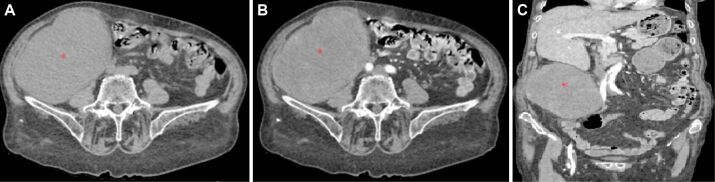

Solitary fibrous tumor (SFT) is a rare mesenchymal tumor that is quite aggressive and prone to recurrence and metastasis. Most SFTs are benign, but the identification of the histological features that define the dedifferentiation of SFTs can predict the aggressiveness of the tumor and the presence of a reserved prognosis. We present a rare case of conventional SFTs with features of malignancy and highlight the diagnostic and therapeutic difficulties related to this case. Computed tomography aspect suggested a possible gastrointestinal stromal tumor. Surgical intervention was performed through median laparotomy and a tumor of approximately 15∕12 cm was found, developed from the level of the right retroperitoneal space, and pushing anteriorly the ascending colon, cecum, and terminal ileum. The immunohistochemical aspect correlated with the histopathological one suggests a SFT most likely malignant. In conclusion, the early diagnosis of SFTs is essential in establishing an appropriate treatment. Immunohistochemistry is indispensable in establishing the diagnosis of SFTs.

Abstract Image